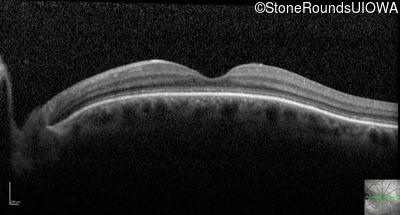

Optical Coherence Tomography - Right - 20/200 sc

Exemplar / OCT Stack

OCT Stack